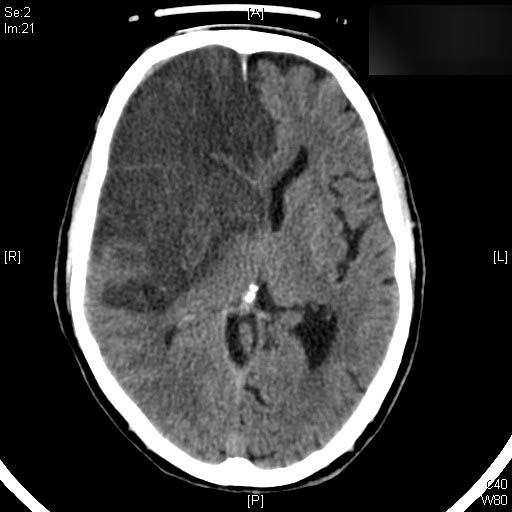

AVC amplio de territorio de A. cerebral media